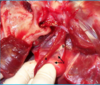

nylon thread passed through mandibular salivary gland duct